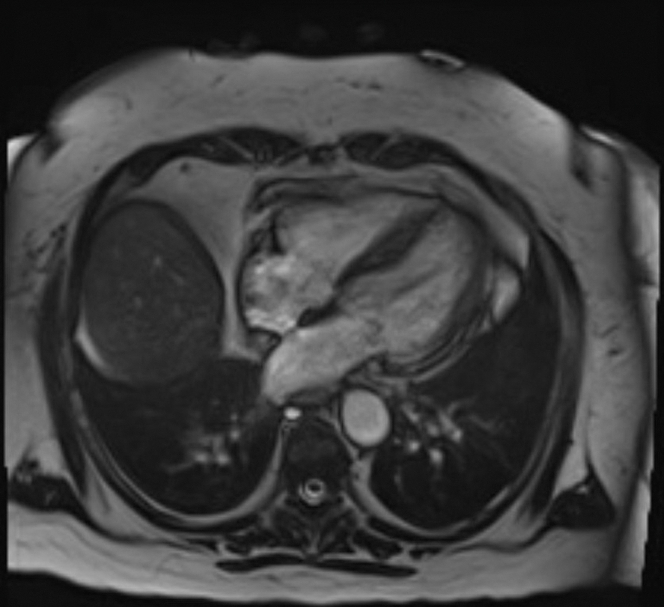

Cardiac magnetic resonance performed on day 13 of presentation showed normal left ventricular size with preserved overall ejection fraction and apical hypokinesis (Figure 3). There were large areas of increased T1 and T2 signal consistent with acute myocardial edema, without significant late gadolinium enhancement. A small area of basal lateral contrast uptake suggested minimal fibrosis or a prior infarct.

Given the markedly elevated cardiac troponin levels, ST-segment elevation on ECG, and cardiogenic shock, she was initially diagnosed with ST-segment elevation myocardial infarction; however, the left heart catheterization ruled against it. The leukocytosis on presentation and past medical history of extensive autoimmune diseases raised the suspicion of myocarditis. The cardiac magnetic resonance performed on day 13 did not show any findings consistent with myocarditis.

The patient’s hemodynamic status improved gradually with intensive supportive care. Serial imaging demonstrated recovery of ventricular function, and the final diagnosis of TTC was confirmed based on cardiac magnetic resonance. On a follow-up echocardiogram performed 4 weeks later, she had complete recovery of LVEF; however, her baseline global longitudinal strain was mildly impaired at −11%.

This report describes rare case of TTC in a postmenopausal woman with a chronic cannabis use who developed cardiogenic shock with CHS. TTC is characterized by transient left ventricular dysfunction in the absence of obstructive coronary disease, typically triggered by physical or emotional stress. Emerging evidence implicates cannabis use as a potential precipitant. Our patient with a history of CHS presented with gastrointestinal symptoms after cannabis use, was found to have severe hypokalemia secondary to intractable vomiting, elevated troponin and NT-proBNP levels, ST-segment elevations on ECG, markedly reduced ejection fraction with left ventricular wall motion abnormalities, and a negative coronary angiography result. Cardiac magnetic resonance performed 2 weeks later demonstrated normalization of the ejection fraction, persistent apical hypokinesis with acute edema, and no contrast uptake consistent with TTC. Notably, she had no identifiable physical or emotional stressor preceding the presentation.